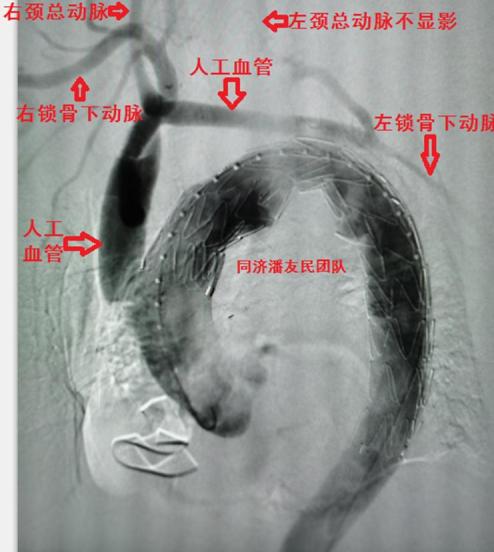

平稳度过保守治疗期,我们设计了杂交手术的方式,从升主动脉接人工血管到头臂干动脉、左颈总动脉及左锁骨下动脉(去分支技术),同期行胸主动脉覆膜支架植入,覆盖主动脉弓上三大分支开口(图7、8)。

释放支架后再次主动脉造影,发现杂交手术重建的左颈总动脉血流仍不通畅,尝试取栓未成功,考虑远端血管堵塞(图9)。